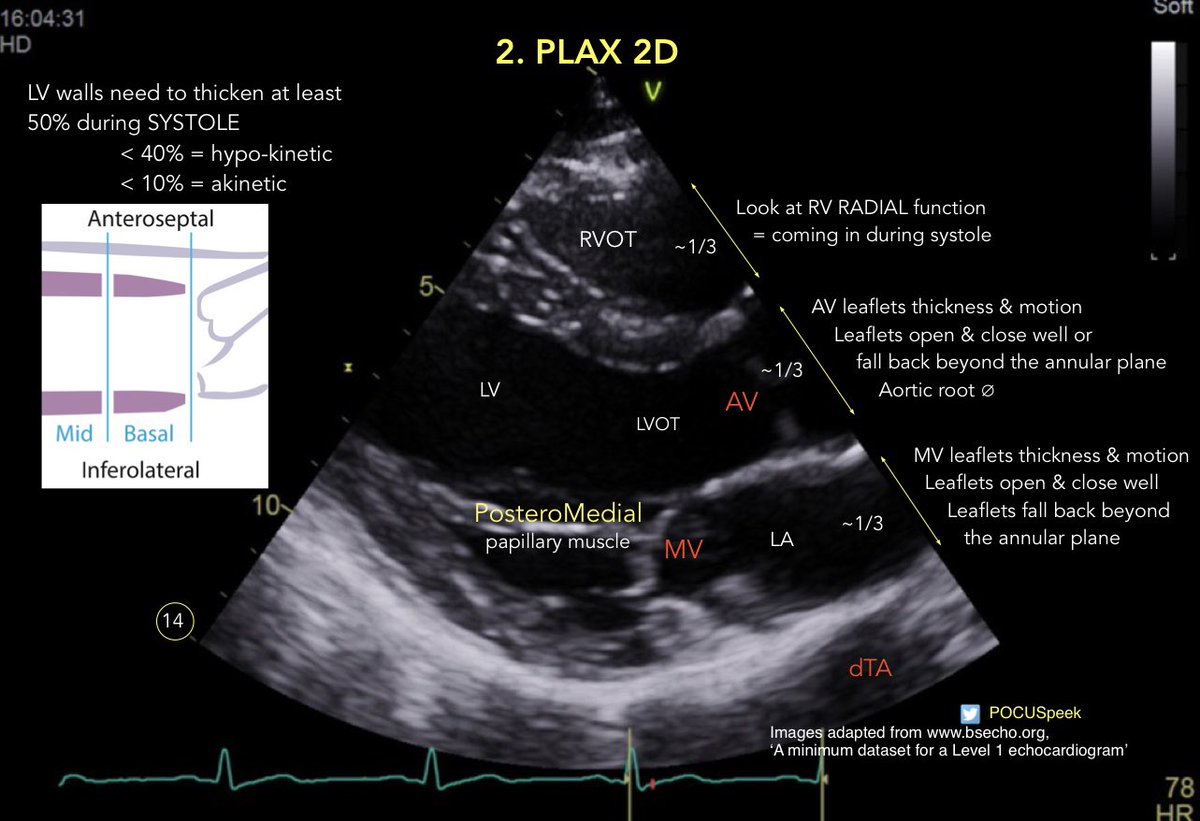

Annotated PLAX views #firstecho #POCUS for @BSEcho level 1 or #FUSICheart @pocusfoamed 🧵 PLAX Deep 2D 👇

🧵 PLAX Deep 2D 👇